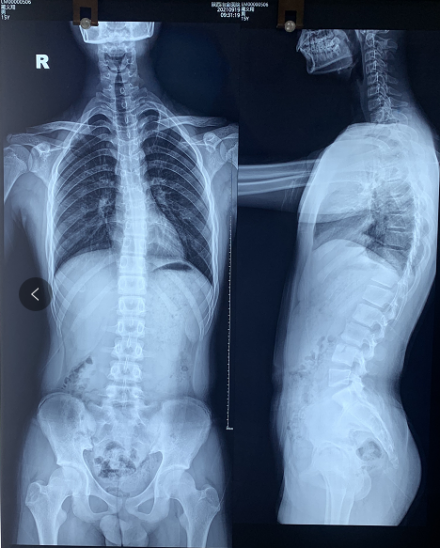

说着安主任就开始认真仔细地给患者进行查体,现症见:脊柱C型改变,左肩高于右肩,左背高于右背;X光片显示:T3-T3左凸右弯17度,诊断为“青少年特发性脊柱侧弯”收入我科进行治疗。

脊柱全长照片: